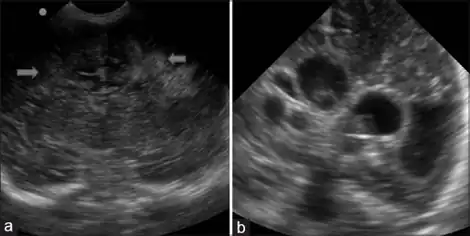

As previously noted, there are often few signs of white matter injury in newborns. Occasionally, physicians can make the initial observations of extreme stiffness or poor ability to suckle. The preliminary diagnosis of PVL is often made using imaging technologies. In most hospitals, premature infants are examined with ultrasound soon after birth to check for brain damage. Severe white matter injury can be seen with a head ultrasound; however, the low sensitivity of this technology allows for some white matter damage to be missed. Magnetic resonance imaging (MRI) is much more effective at identifying PVL, but it is unusual for preterm infants to receive an MRI unless they have had a particularly difficult course of development (including repeated or severe infection, or known hypoxic events during or immediately after birth).[5] No agencies or regulatory bodies have established protocols or guidelines for screening of at-risk populations, so each hospital or doctor generally makes decisions regarding which patients should be screened with a more sensitive MRI instead of the basic head ultrasound.